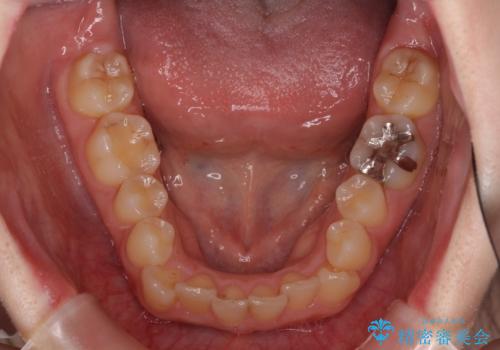

- 顕著な八重歯など、上下前歯のデコボコとスペースを気にして来院された患者様です。

八重歯改善には第一小臼歯の抜歯が必要であり、移動量が多いことから補助装置により八重歯を引き込むこととしました。

インビザラインでの治療をご希望であったので、インビザラインにて行うこととしましたが、右側前歯の改善にはワイヤー矯正が必要となる可能性があることをお伝えした上で治療を開始しました。

補助装置だけでなく、部分的にワイヤー矯正も使用しましたが、上下のスペースは改善しきれず、側切歯(前から2番目の歯)や顕著な八重歯は、インビザラインで治療するには限界があることがよく分かりました。

より良い仕上がりを希望される場合には、ワイヤー装置による矯正治療がお勧めとなります。